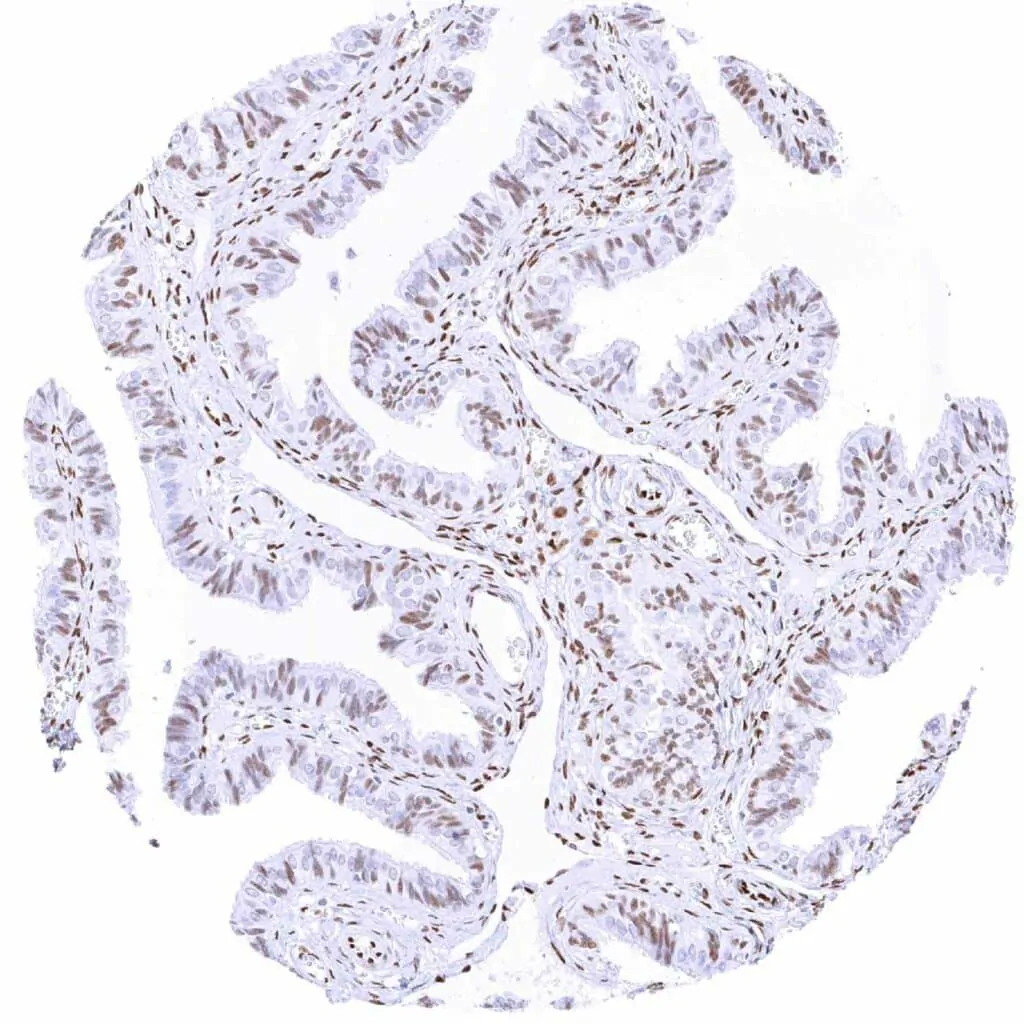

Uterus, endometrium (proliferation) – Moderate to strong TLE1 staining of epithelial and stromal cells

Uterus, endometrium (secretion) – Moderate to strong TLE1 staining of most epithelial cells